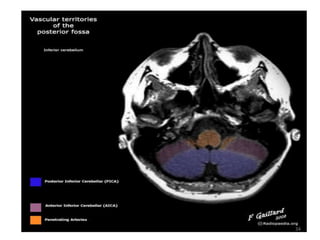

• Arterial supply:

-Superior cerebellar artery<Distal Bacillar Artery

-Anterior inferior cerebellar artery<proximal Bacillar

Artery

-Posterior inferior cerebellar artery<Vetebral Artery

Blood Supply of Cerebellum

31